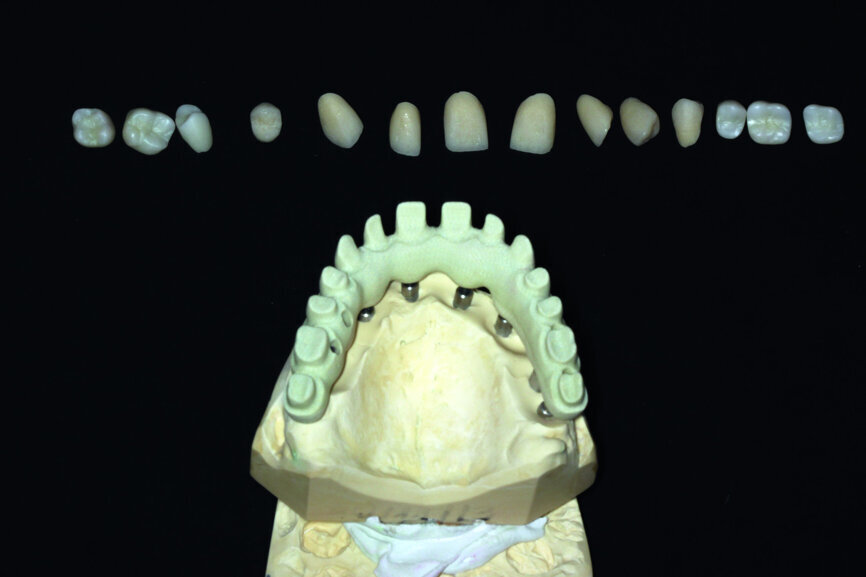

Fig. 13: Porcelain crowns prepared for testing.

Fig. 14: Porcelain crowns based on a model prior to veneering by means of a pink composite.

After this has been done, the next step consists in testing the almost ready-made crowns before the final glazing and before attaching it onto the model. As a result it is possible to make corrections, should they be necessary. Of course, one should check the proper match-up and the aesthetics on the model (Figs. 13 & 14).